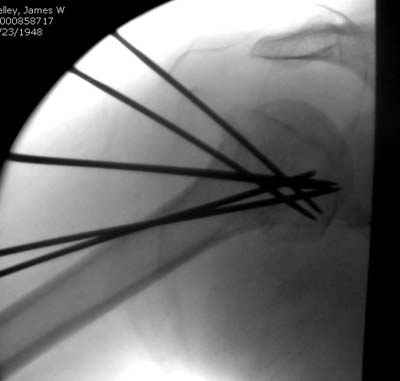

Пока я пользуюсь методикой принятой у нас (методика Сиэтла), также перкутанный спицевой метод, только сцицы 2.8 мм с резбой на конце.

Здесь случай перелома-вывиха плеча, больному 56 лет, после "дважды" закрытой неудачной репозиции, опять же ургентно взяли в операционную, после полного общего обезболивания попытались сделать репозицию, и фиксацию провели спицами.

Больной находился в повязке, примерно напоминяющей косыночную, рекомендованы движения в локтевом суставе и маятниковые движения в плече, спицы удалены в три недели (были случаи миграции)